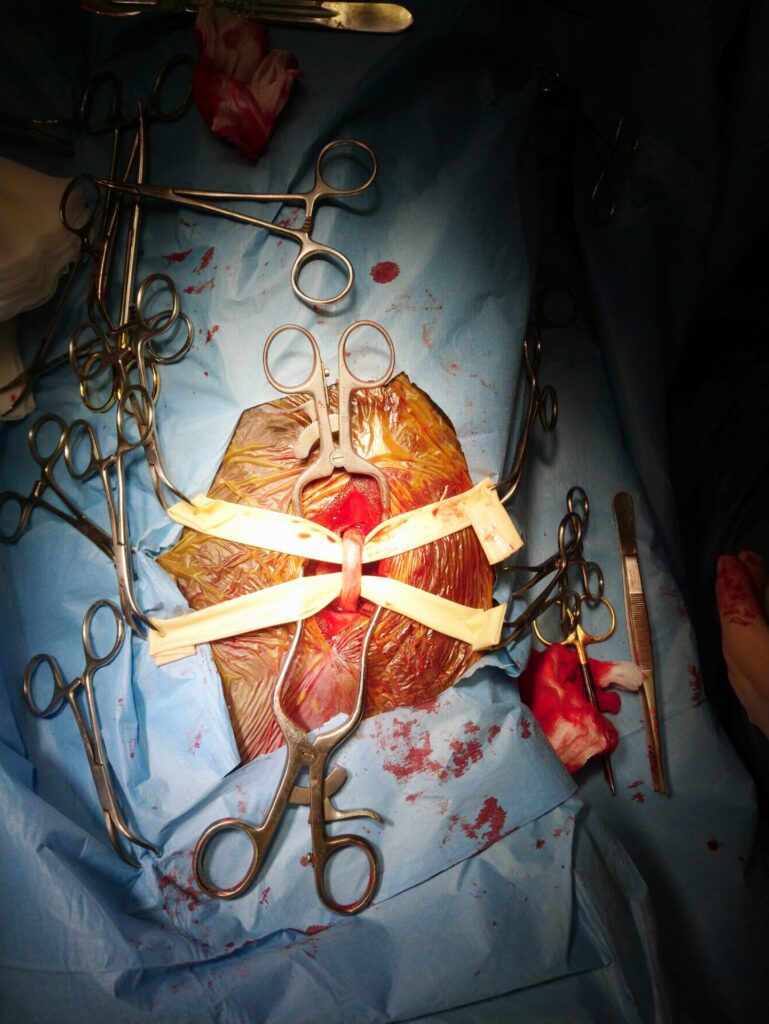

Jakmile se plíseň rodu Aspergillus uchytí ve vzdušných vacích, nalezne zde ideální místo k množení. Plísně mají rády teplo, a proto se obvykle usídlují v blízkosti velkých krevních cév, které vedou vzdušnými vaky. Tyto tepny jsou pro plísně zároveň ideálním zdrojem živin. Nejčastěji se plísně nacházejí v blízkosti vnitřní větve krkavice (obr. 3 a, b, obr. 4).